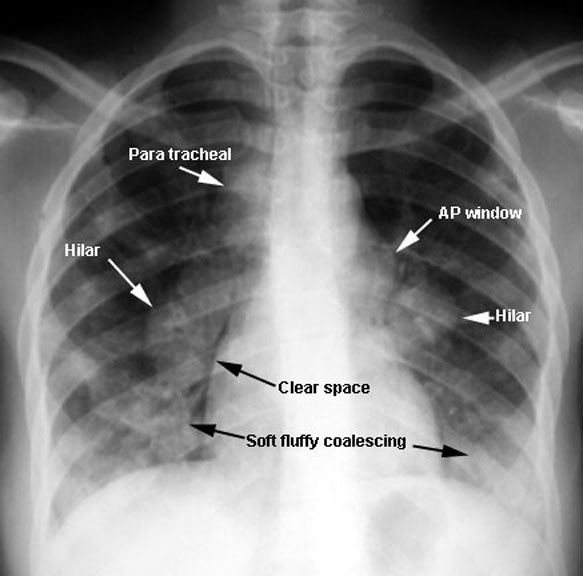

Sarcoidosis

Alveolar Form

• Symmetrical hilar nodes

• Mediastinal nodes

• Multiple bilateral mass densities with alveolar features

• Soft coalescing

Labeled